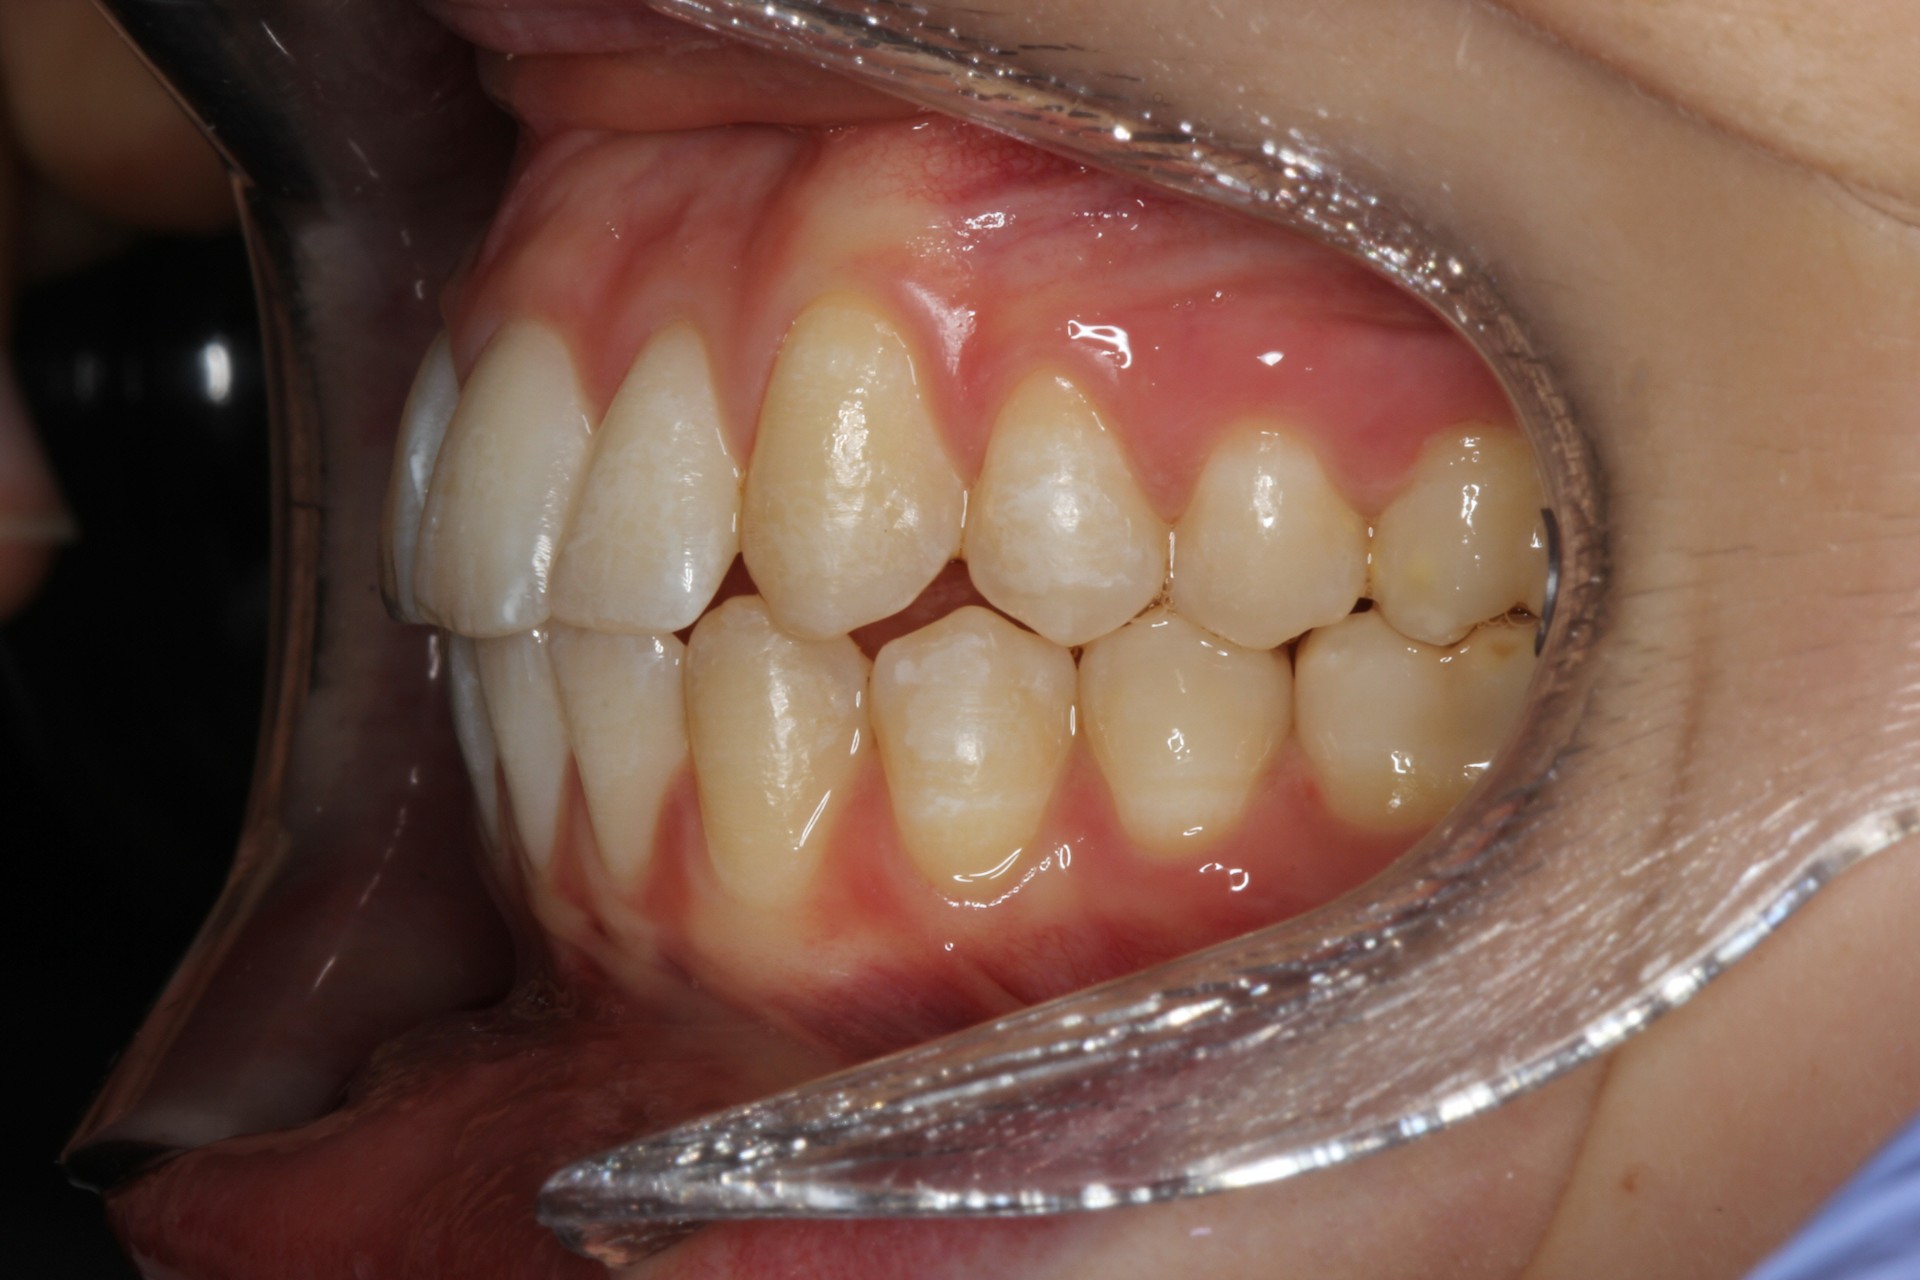

Protruding front teeth – Child case